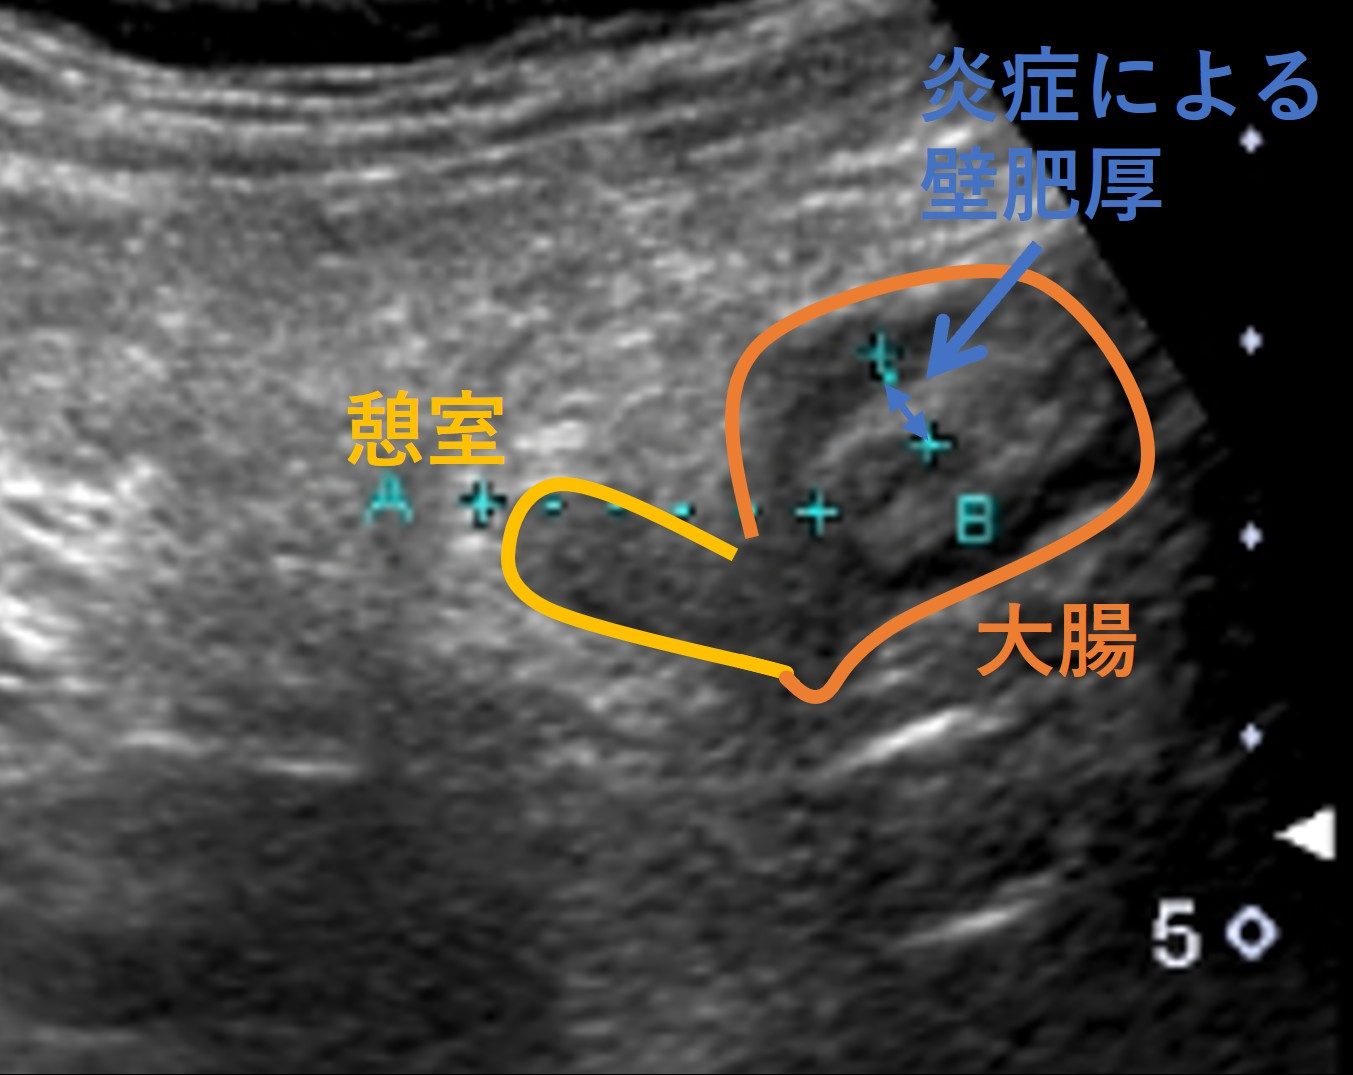

腹部エコーを行うと、左下の痛む場所に一致してS状結腸の憩室(黄色部分)と周囲の大腸の壁の肥厚(図:青部分)が描出されました。

血液検査でも強い炎症反応が認められたことから、大腸憩室炎と診断しました。